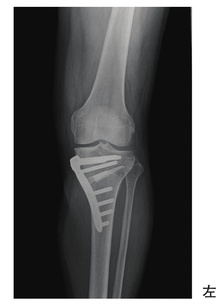

60歳の男性。内側型の変形性膝関節症に対して手術療法が行われた。術後のエックス線写真を別に示す。骨癒合を促進させるために最も優先度が高い治療法はどれか。

XK-H07QJ9O

1

温熱療法

2

牽引療法

3

超音波療法

4

電気刺激療法

5

電磁波療法